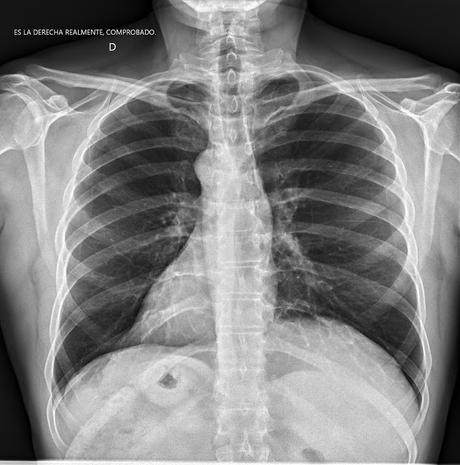

La radiografía que vemos más abajo corresponde al mismo paciente: como puede verse su corazón se sitúa a la derecha, hasta el punto de que el radiólogo añadió la nota que puede leerse en la esquina superior: "ES LA DERECHA REALMENTE, COMPROBADO"

Efectivamente se trata de un SITUS INVERSUS TOTAL, esto es: de un paciente que tiene TODOS los órganos invertidos: el corazón a la derecha, el hígado a la izquierda, el estomago y el bazo a la derecha, etc...